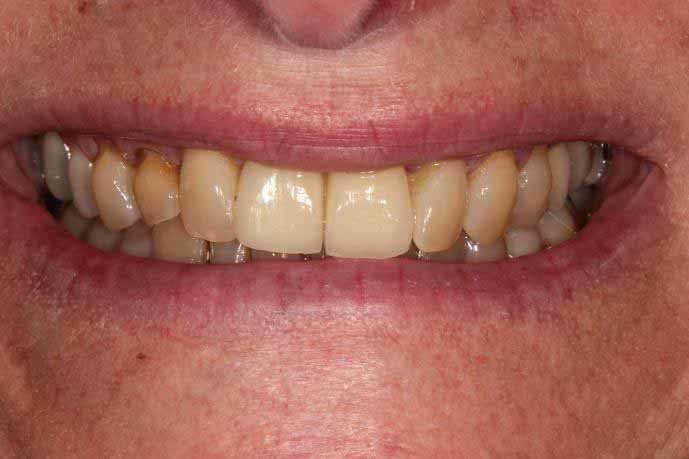

Upper Front Tooth Implant

This patient had broken their upper front tooth and the exisitng dental crown had fallen off. The underlying root was unfortunatley irreparable.

The dental root was subsequently removed and an implant placed at the same time. The implant had a temporary crown placedon the same day.

The ‘After’ photos shows the final crown that was made after 3 months. The implant crown was made to match the form and colour of the exisiting teeth to give an overall natural aesthetic finish.